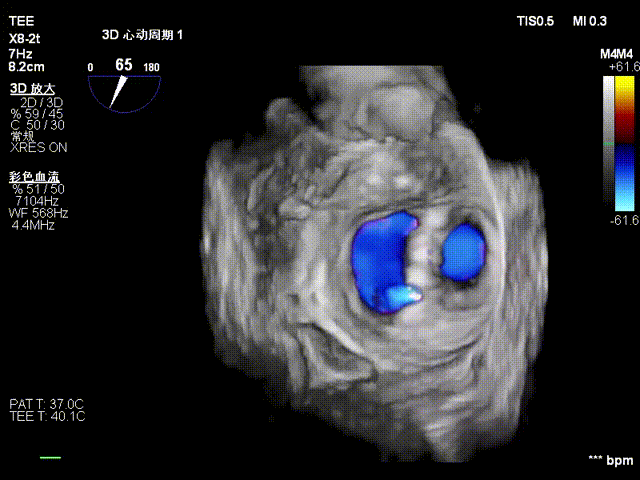

在全麻下,于心尖入路完成ValveClamp®装置植入。术中多学科团队密切配合,超声全程实时指导操作。最终,于2偏3区成功植入一枚Ⅲf夹子,一次夹合完成。前叶夹合量12mm,后叶夹合量10mm,反流降至1+,导管操作时间30分钟。术后平均跨瓣压差3mmHg。

术中剪影